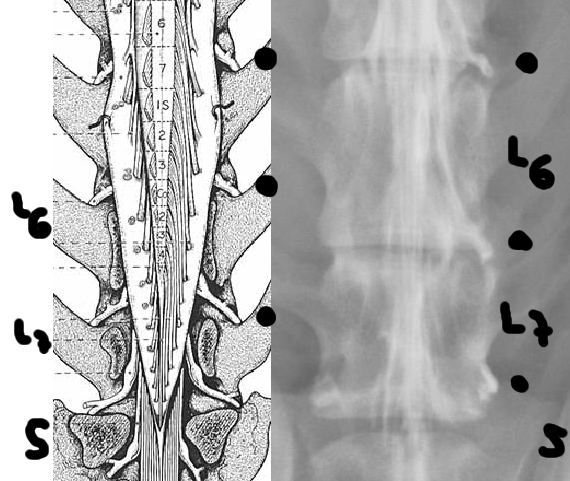

Radiografía con contrastes: mielografía por saco dural | |||||||||

![]() por Juan M. Griñán. Veterinario ![]() comparativa entre una mielografía (mostrando la aguja) y una resonancia magnética, secuencia SE T1w (mostrando donde está el saco dural, sitio para la inyección del contraste). Nótese la extravasación del contraste yodado en la mielografía. | |||||||||